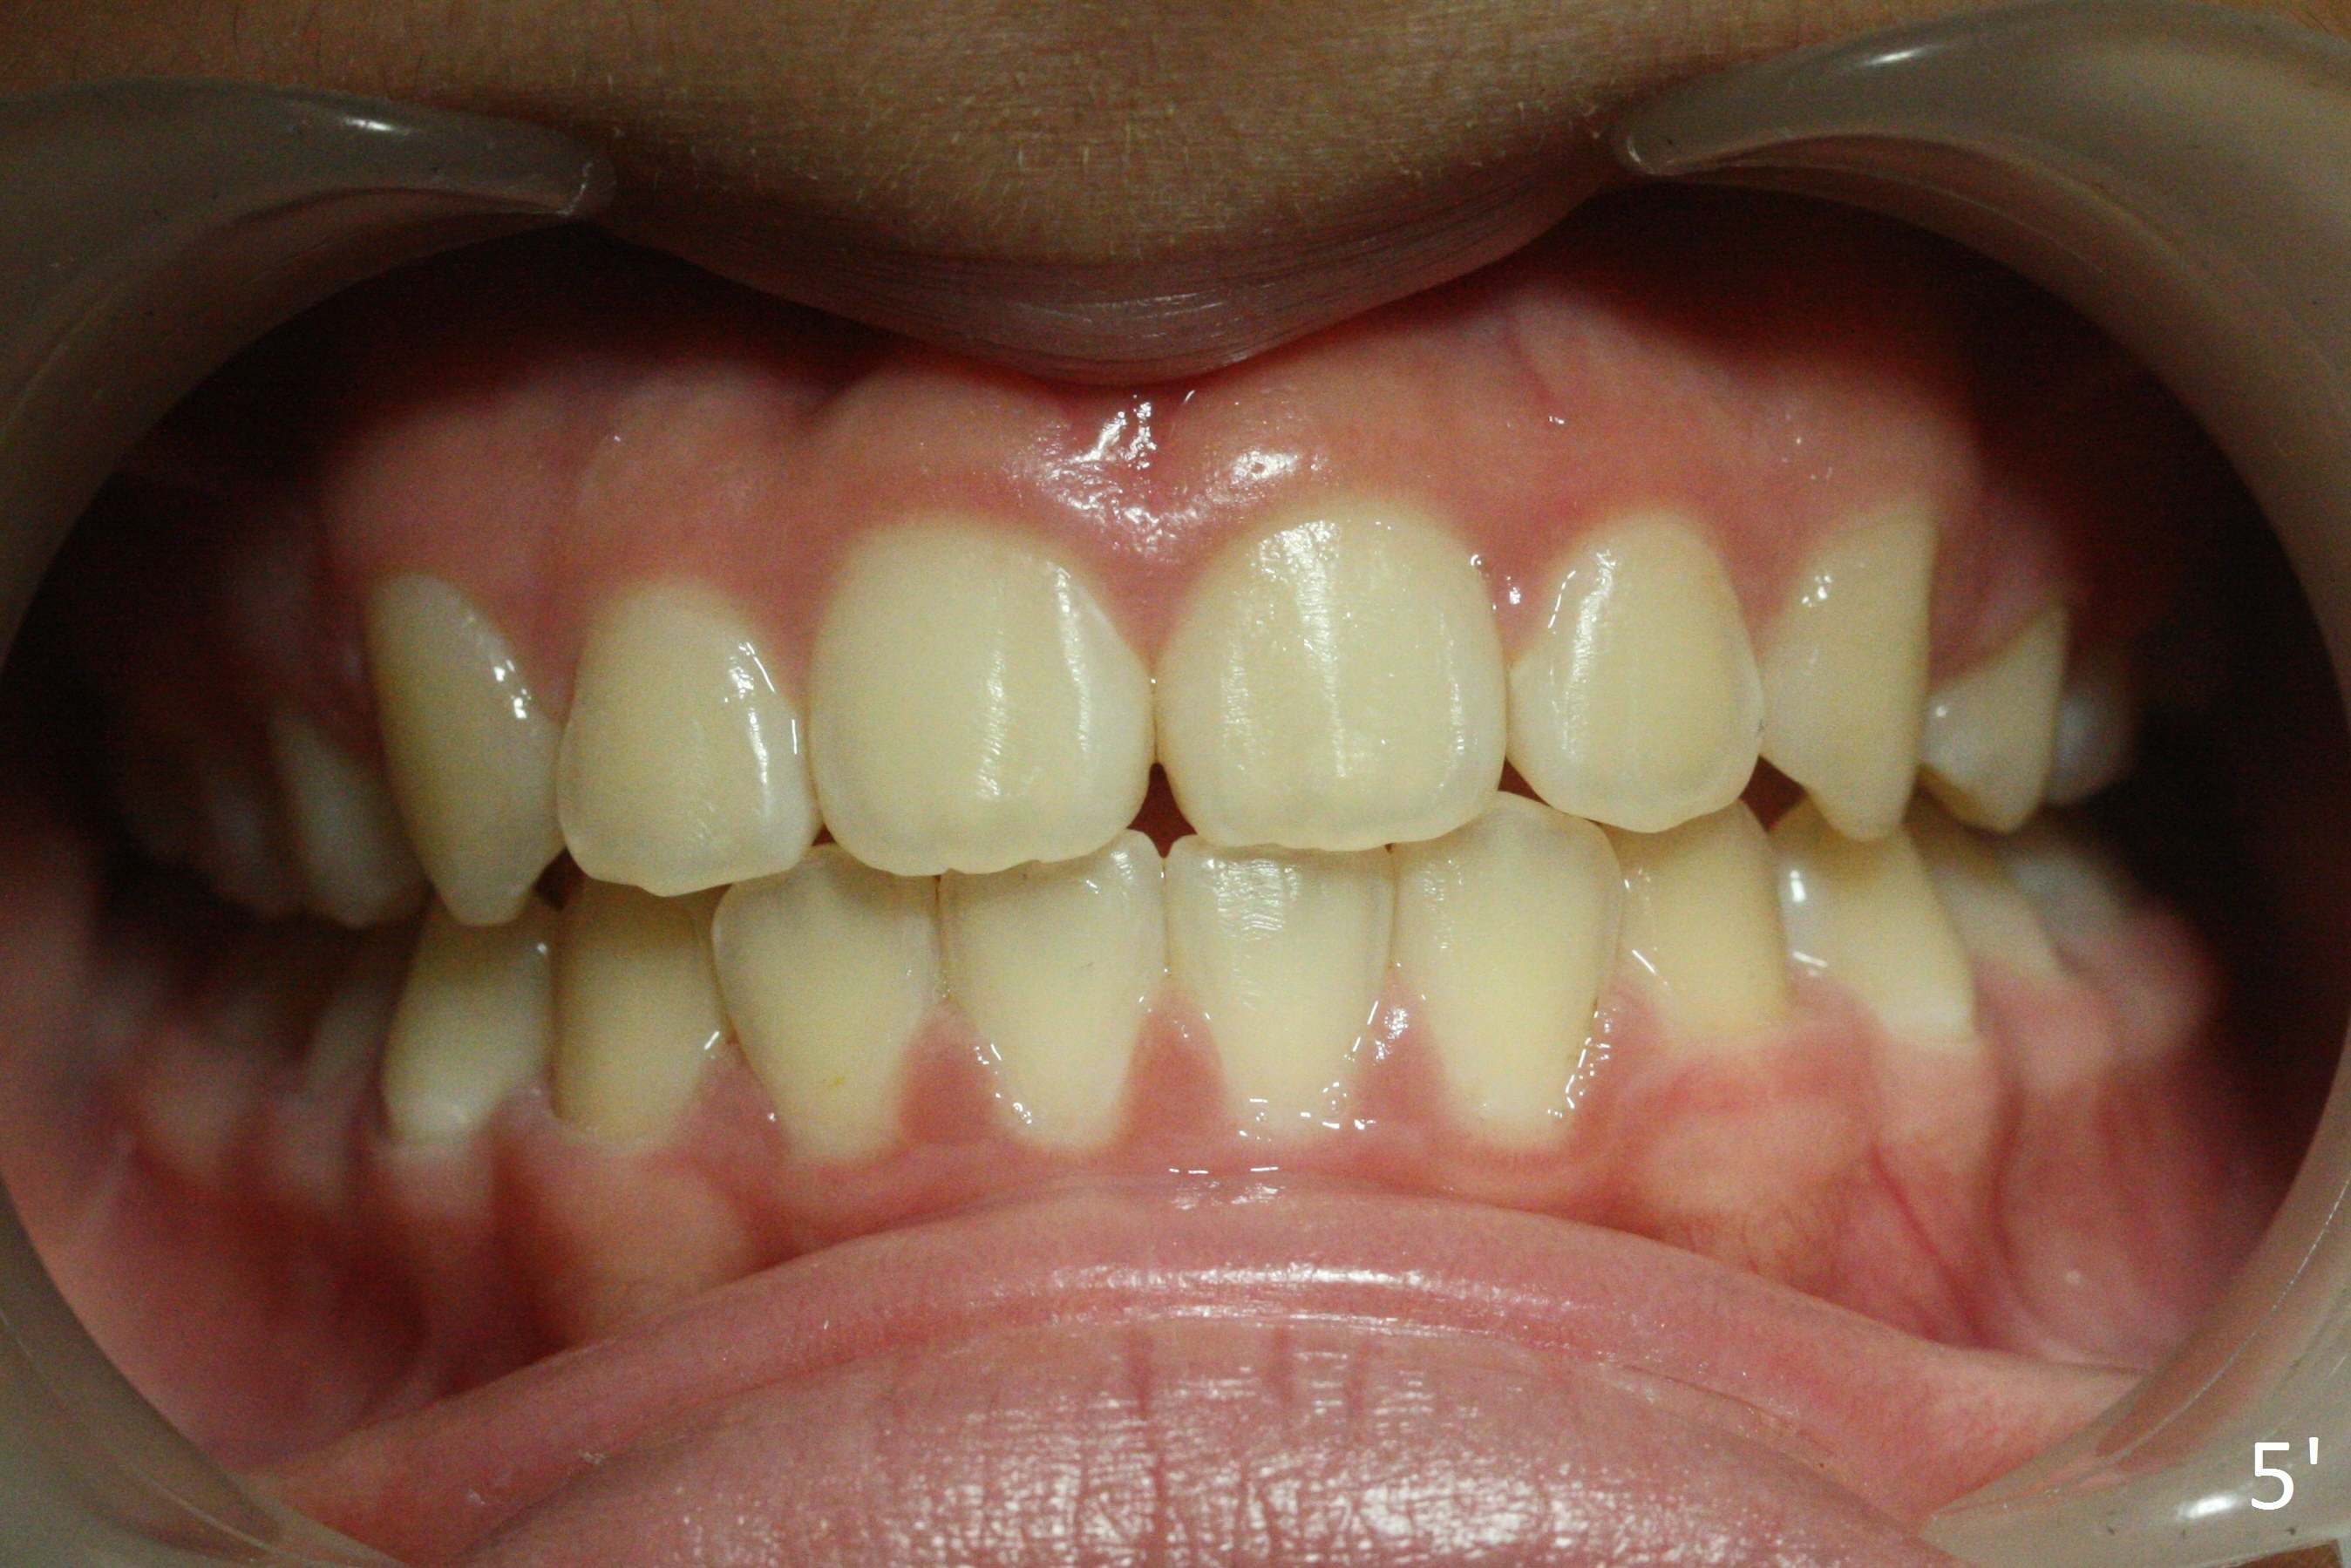

A 12-year-old girl has Class II Division I malocclusion (Fig.5,6) with protrusion of the upper lip (Fig.3). With extraction of the upper 1st bicuspids, postop facial profile improves (Fig.3', 4').

Make sure that the camera is parallel to the imaginary occlusal plane (Fig.5') when intraoral occlusal frontal view is being taken.